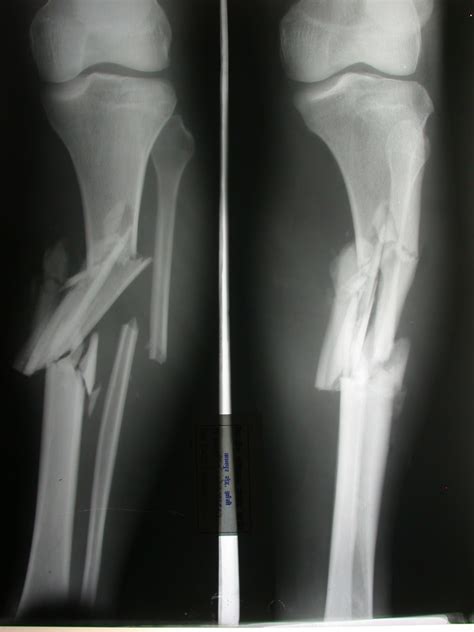

• Imaging Tests: X-rays are the primary imaging tool used to diagnose bone fractures. They can provide clear images of the bone structure, allowing the healthcare provider to determine the type and extent of the fracture. In some cases, additional imaging tests such as CT scans or MRI may be required for a more detailed assessment.